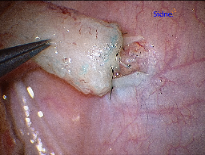

Epididymovasostomy

Epididymovasostomy is required during vasectomy reversal when there is absent sperm in the vas deferens. This signifies that a secondary epididymal obstruction has developed upstream from the vasectomy site. This situation is encountered in approximately 40% of individuals after a vasectomy. Epididymovasostomy can only be performed using a high powered operating microscope, under general anesthesia, by microsurgeons using the finest suture (10-0 nylon).